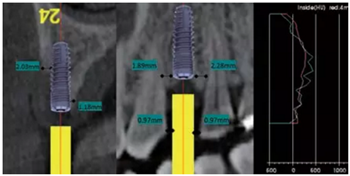

術(shù)前拍攝錐形束CT并做種植方案規(guī)劃。從圈紅處可以看出頰側(cè)骨組織不夠致密,建議備完孔后再做小翻瓣以觀察窩洞頸部的情況,圖2中的粉紅色及藍(lán)色HU值曲線顯示種植體內(nèi)部及其周圍的骨密度不高,為四類骨質(zhì),因此術(shù)中應(yīng)通過控制備孔的直徑或深度,以使種植體獲得較佳的初期穩(wěn)定性。

圖2 種植方案的規(guī)劃:a.頰舌側(cè)方向的截面圖,頰側(cè)圈紅處骨質(zhì)較疏松;b.近遠(yuǎn)中方向截面圖;c.種植體周圍的骨密度